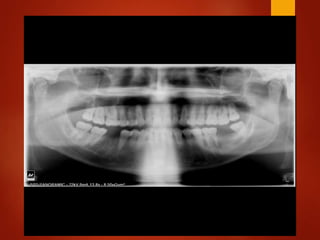

El documento es un registro médico odontológico que muestra las fechas de las visitas de un paciente al centro de salud El Raval, incluyendo exámenes y tratamientos realizados como la extracción de cálculos salivales en abril y mayo de 2012.